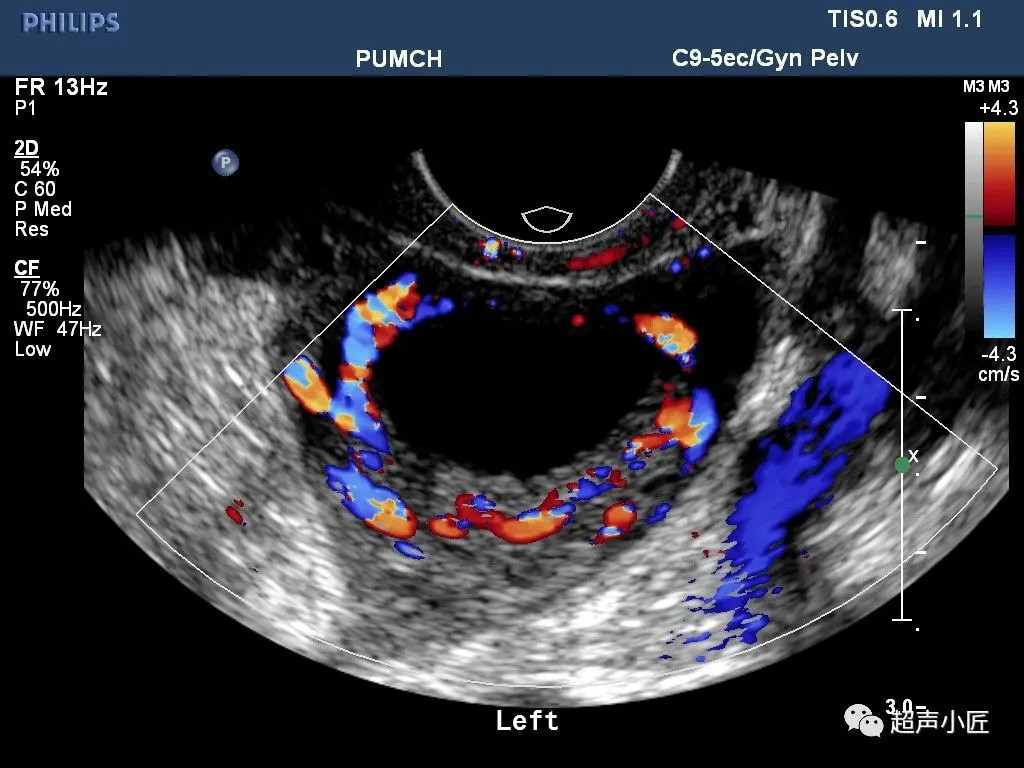

●黄体囊肿(多见于子宫内膜分泌期或妊娠早期):大小多为2-3cm或更大;个别黄体囊肿可破裂出血而出现急腹症。

●黄素囊肿:囊肿较大;呈不规则形、叶状;内部可有分隔,呈车轮状;壁薄而光滑;隔壁上可显示血流信号。